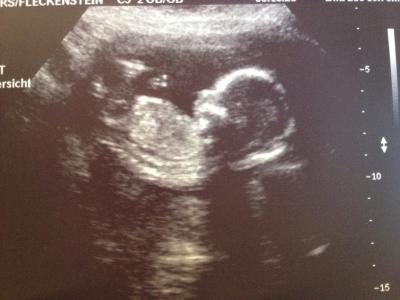

Hallo, Ich war heute wieder bei meiner FÄ und es ist alles gut entwickelt. Sie hat festgestellt, dass ich eine Vorderwand Plazenta habe. Das hatte ich auch schon bei meinem Sohn. Sie hat auch nach dem Geschlecht geschaut, konnte es aber nicht richtig sehen. Sie würde jetzt auf ein Mädchen tippen, weil man nichts gesehen hat was für einen Jungen deutet. Beim nächsten zeigt es sich vielleicht besser und dann kann sie es genauer sagen. Und ein Bild hat sogar meine Tochter (7 Jahre) bekommen. Lg Laura

Bild zu Heute FÄ-Termin gehabt! - Forum für April - Mamis

Und es trinkt schon Fruchtwasser!